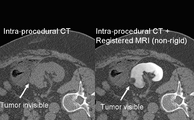

B-Spline Registration in Slicer 3.6 allows for non-rigid registration between pre-procedure MRI and intra-procedure CT images during CT guided tumor ablation in the liver. It provides increased tumor visualization during the planning, targeting and monitoring phases of the ablation procedure.